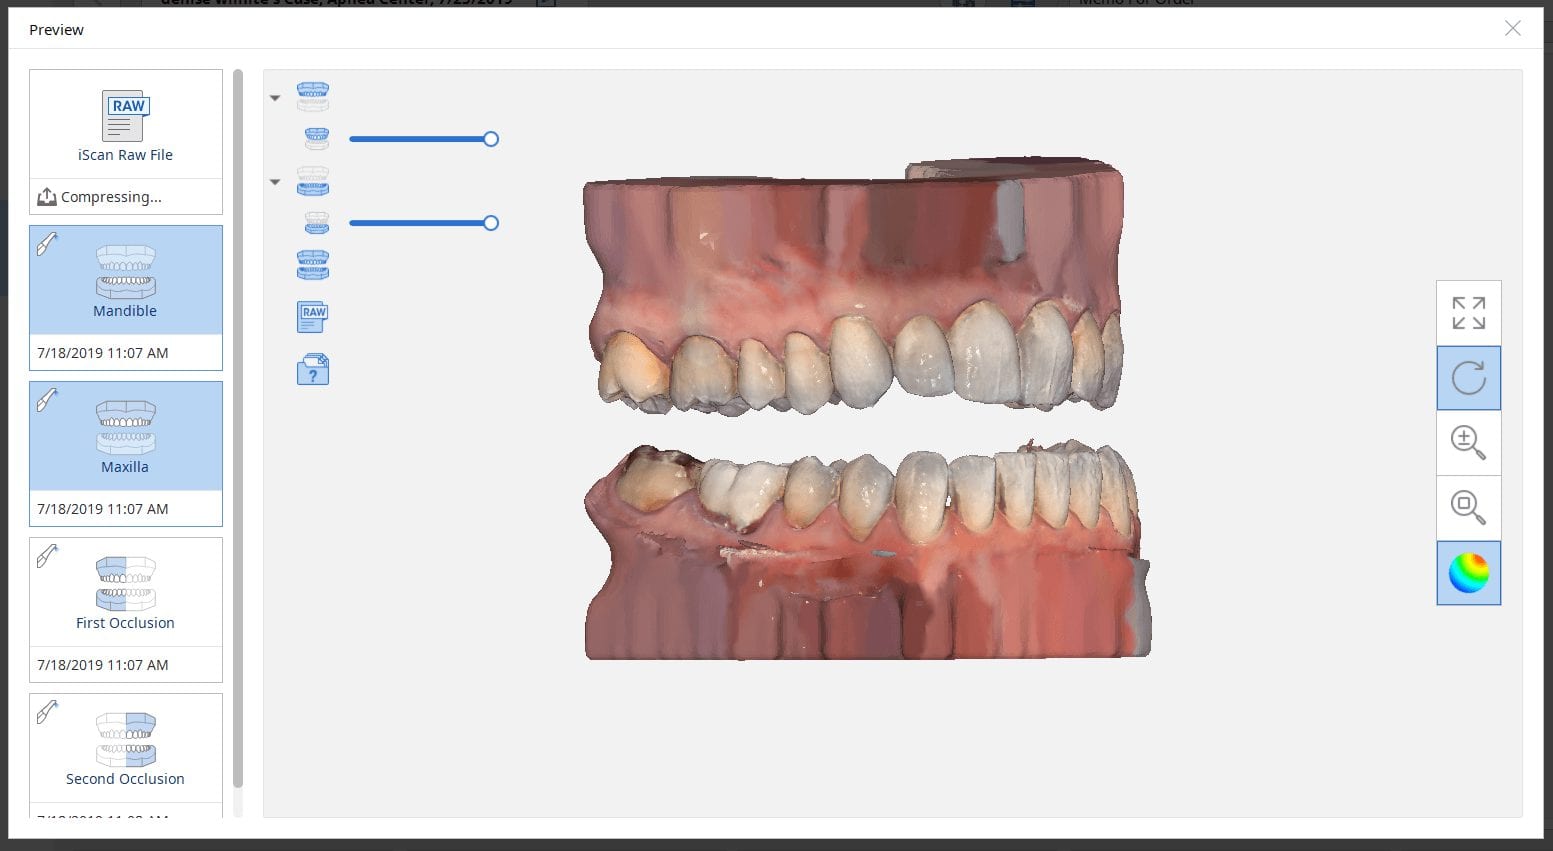

Capturing Multiple Occlusal Relationships for the Maxilla and the Mandible with the Medit i500

July 18, 2019There are multiple ways one can capture the bite for a patient. In this clinical case, we focus on the easiest way to capture two bites (one in maximum intercuspation […]